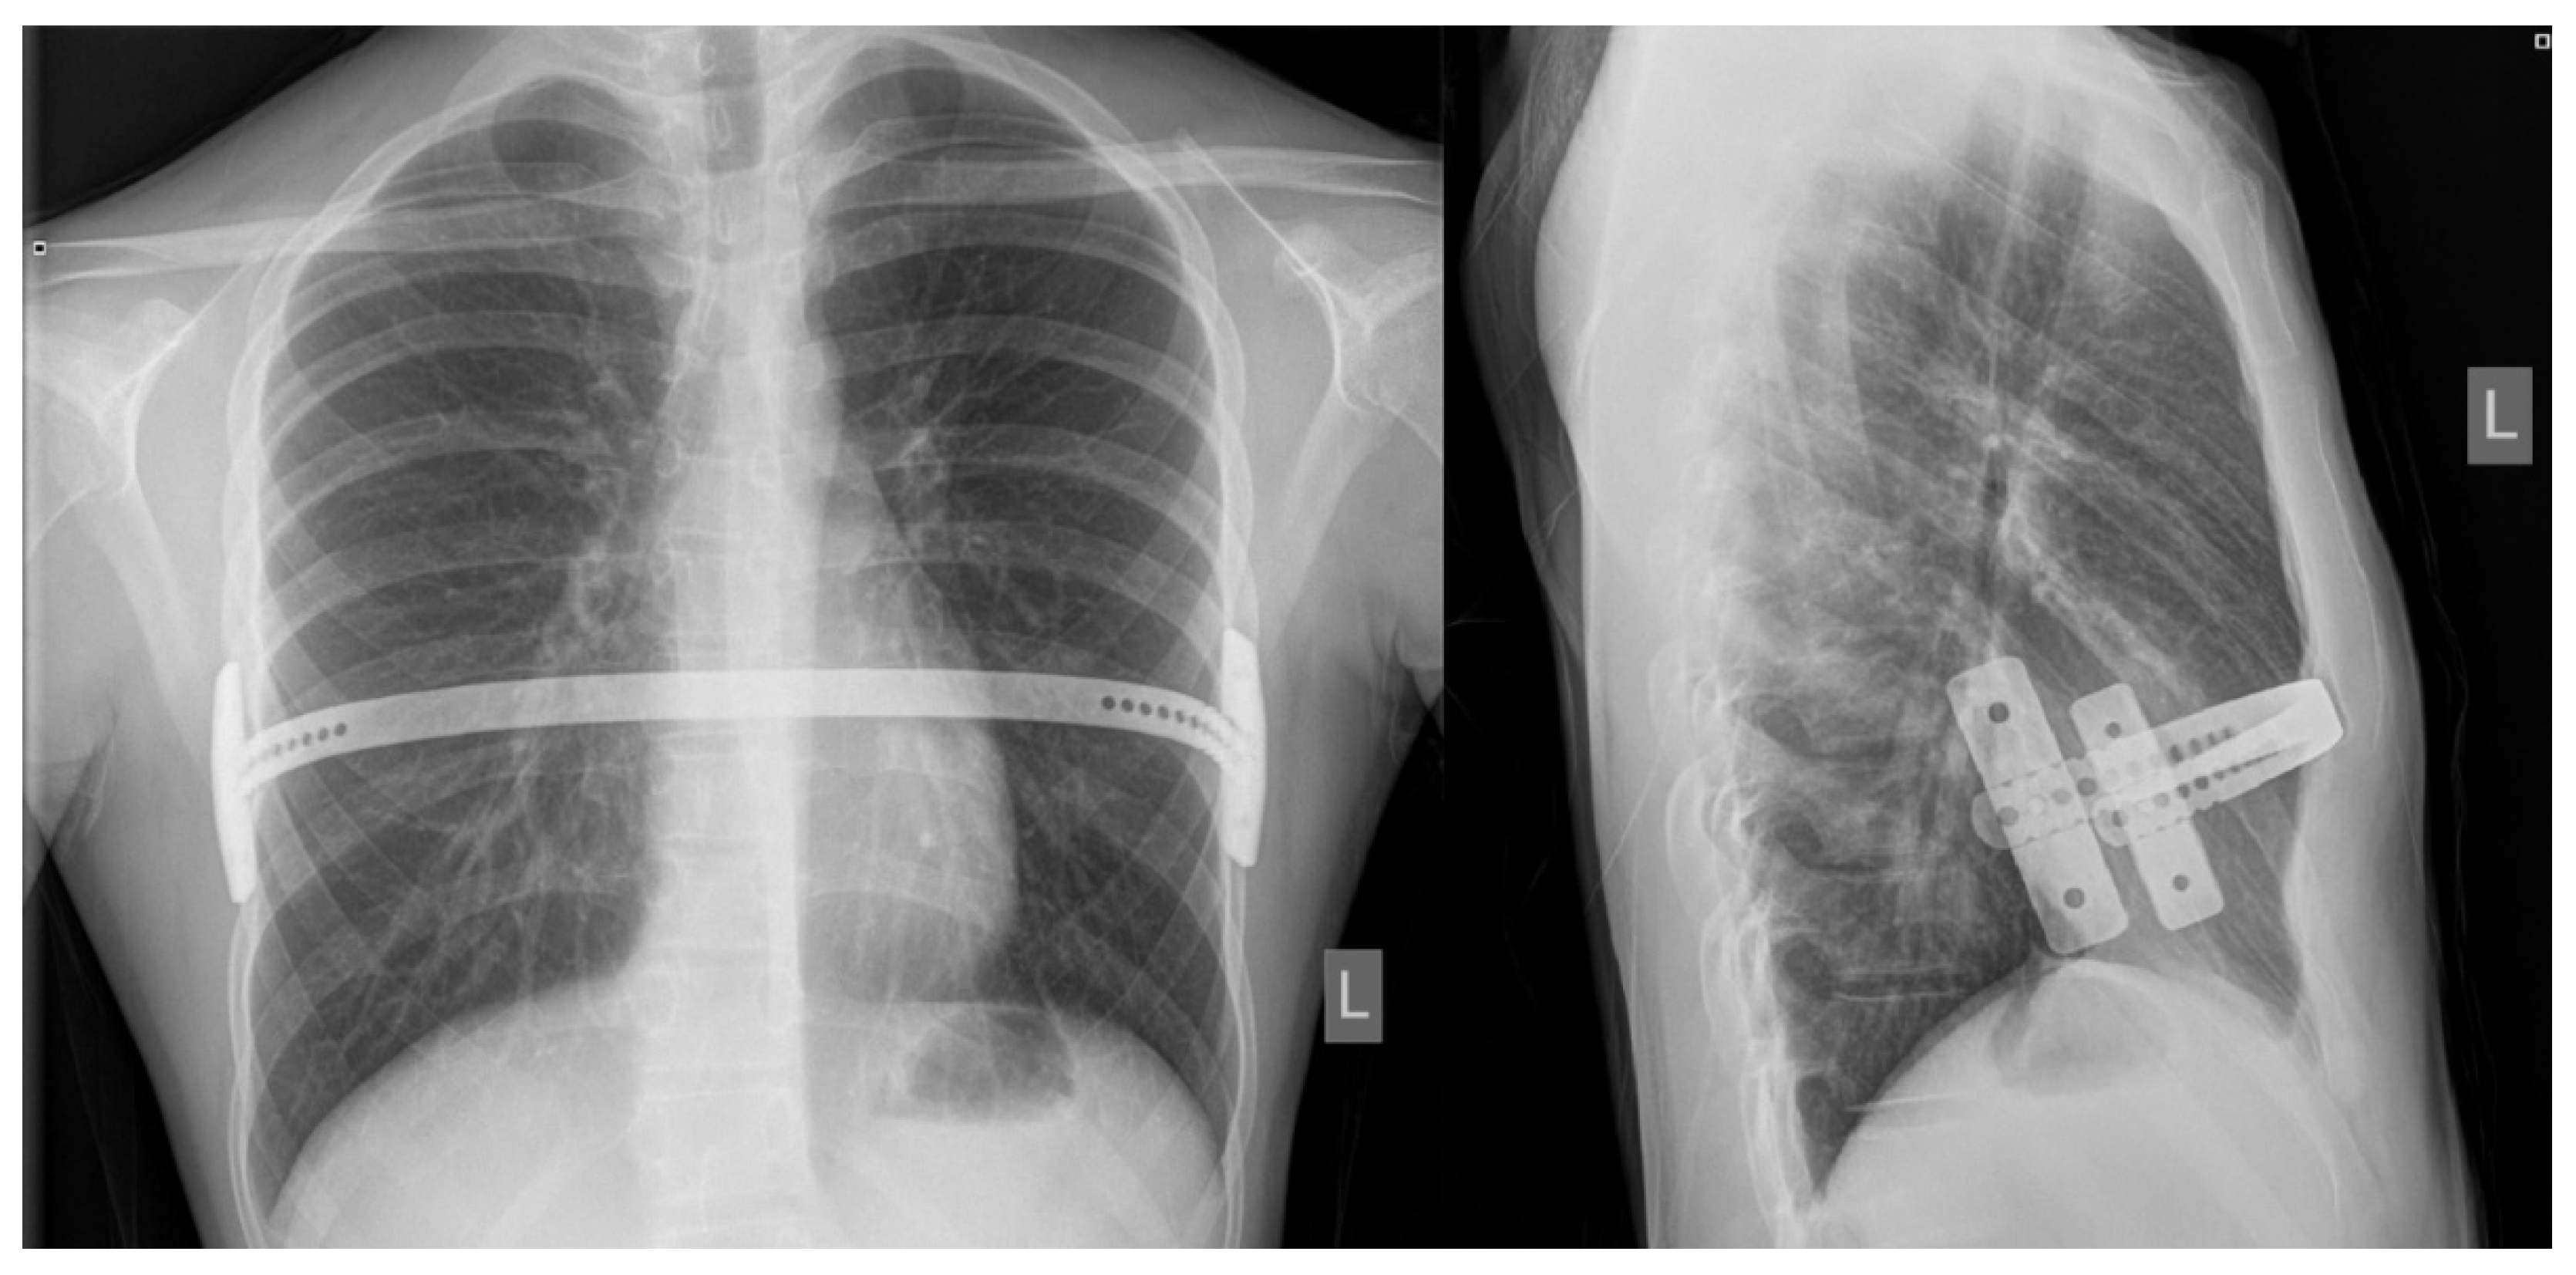

Figure 3. Bar position at postoperative chest X-ray: posteroanterior (left) and laterolateral (right) views.

After the surgical procedure, the patients are observed in the intensive care unit until they areoff opioid intravenous medications and after the eventual early complications are resolved. Patient-controlled analgesia, using morphine (Morphine hydrochloride, Alkaloid, Skopje, Republic of North Macedonia) or fentanyl (Fentanyl Piramal, West Drayton, UK), is started in the operating room and is gradually switched to oral pain medications over the next 2–3 days. Other strategies for controlling postoperative pain include oral non-steroidal anti-inflammatory drugs (NSAIDs): ibuprofen (Brufen, AbbVie, Campoverde, Italy), metamizole sodium hydrate (Alkagin®, Skopje, Republic of North Macedonia), paracetamol (Perfalgan, Bristol-Myers Squibb Pharmaceuticals limited, Bristol, UK),and anxiolytic/spasmolytics such as diazepam (Normabel, Belupo, Koprivnica, Croatia). Stool laxatives and emollients are given to prevent constipation while intravenous fluids and proton pump inhibitors are given to reduce the side effects of oral NSAIDs on the gastrointestinal tract. Pulmonary hygiene using an incentive spirometer begins a few hours after surgery and continues for several weeks to prevent lung collapse and pneumonia. Respiratory therapists are helpful in providing guidance on the proper use of the stimulus spirometer. Recovery begins on the first postoperative day with the help of a physiotherapist;on the same day, a chest X-Ray is performed to define possible early complications (pneumothorax, subcutaneous emphysema or effusions) and bar position (Figure 3). Patients are instructed to lie on their backs and to avoid any pressure on the sides of the chest during the first six weeks after surgery. Patients are discharged homeafter they are free from intravenous analgesics. At home, patients are encouraged to walk as much as possible and to do deep breathing exercises using a stimulating spirometer several times a day. Patients havefollow–up appointments at the outpatient clinic after the first, second, fourth, and sixth weeks following surgery, and any possible complications are noted. After the six and twelve month periods, another control exam is conductedat outpatient clinics as a follow-up to define the degree of pain, medication use and duration, and quality of physical therapy. Patients were screened for surgical complications according to Clavien–Dindo classification [14].